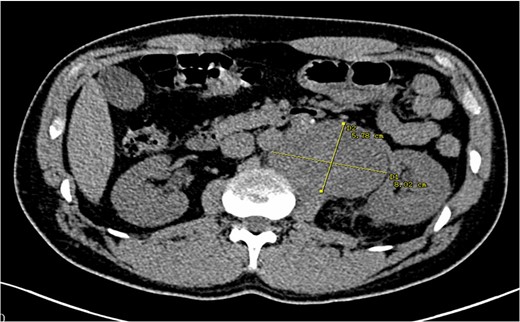

The lumbar spine MRI obtained previous to the chemonucleolysis reported a discopathy and lymph node enlargement in the retroperitoneal area. Although the discopathy was resolved, the persistence of lumbar pain called for a different approach. During the workup, an urotomography scan was performed, which confirmed multiple retroperitoneal masses in the left paraaortic region measuring 10 × 8 × 6 cm3. There were satellite lymph nodes around the retroperitoneal mass and the left psoas causing lateral displacement of the left kidney, compressing the pyelocaliceal system conditioning hydronephrosis (Fig. 1). Next, a testicular sonogram showed the left testicular heterogeneous parenchyma, with high vascularity and irregular borders, with a size of 28 × 23 × 14 mm3 and a volume of 4.9 cm3. Evaluation of the right testicle was unremarkable. These findings were suggestive of a primary TGCT. Laboratory studies revealed a serum alpha fetoprotein of 15 115 ng/dL (normal value <20 ng/dL), β-human chorionic gonadotropin (β-HCG) of 11 IU/L (normal <0.5 IU/L) and lactate dehydrogenase of 394 U/L (normal value <250 U/L). As part of treatment, the patient underwent left radical orchiectomy without any complication and the specimen was sent for histological analysis. Pathology results showed subtotal atrophy of the testis with extensive fibrosis, multifocal calcifications, focal hemorrhage and Leydig’s cell hyperplasia. Extensive recent hemorrhage in the spermatic cord and epididymis was evident, without pathological alterations. There was no evidence of germ cell tumor, confirming spontaneous tumor regression (Fig. 2). After reassessment, a cystourethroscopy with placement of a double J catheter was performed to resolve the secondary hydronephrosis due to obstructive uropathy. Subsequently, the patient began first-line chemotherapy with four cycles of bleomycin, etoposide and cisplatin (BEP) protocol. Hiccups, nausea, constipation and alopecia presented as adverse events that were managed with symptomatic medications. By the time of the submission of this case report, the patient had concluded his fourth BEP administration.

Urotomography scan with evidence of a retroperitoneal mass that displaces the left kidney with hydronephrosis. The calculated volume was 10 × 8 × 6 cm3.